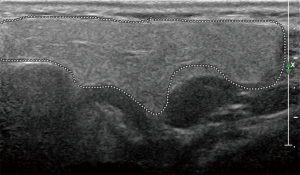

The principal ecostructural abnormalities detectable by SGUS are the following: parenchymal non-homogeneity, hypo-anechoic or hyperchoic areas (due respectively to cysts or calcifications), size variations, irregularities in glandular profiles and the presence of intra- or periglandular lymph nodes (19) (Figures 3-5). As highlighted by several authors (9,20), the most relevant SGUS alteration of pSS is the parenchymal inhomogeneity detectable bilaterally. This ultrasound finding, is the one that has shown the greatest agreement with the alterations documented with the scintigraphy of the salivary glands, sialography, and minor labial salivary gland biopsy (LSGB) (21,22). At the level of the parotid and submandibular glands, SGUS shows the best relationship of sensitivity to specificity, with a positive predictive value of 72.0% and a negative predictive value of 96.0% (23). Compared to contrast sialography and to salivary gland scintigraphy, SGUS showed higher sensitivity (75.3%, 72.7% and 70.1%, respectively), with similar specificity (83.5%, 84.9% and 82.3%, respectively) (7). Ultrasound findings of hypoechoic, multiple, circumscribed or confluent areas and/or multiple cysts correspond to a histological pattern of ductal ectasia surrounded by lymphocyte infiltrate or dilated glandular lobes surrounded by lymphocyte aggregates. In particular, Kawamura et al. (24) and Salaffi et al. (7,12) demonstrated that the anomalies documented at SGUS are strongly related to histological changes (12), and that the SGUS score proposed for classification is well correlated with sialographic classifications (12). Cornec et al. (15) have verified that morphological abnormalities of the salivary glands can be detected early in the course of pSS. The diagnostic characteristics of the SGUS also seem not to vary during the disease. Applying an ultrasound cut-off of 5, the proposed SGUS scoring system was slightly less specific (85.7% vs. 77.9%) but more sensitive (94.9% vs. 98.7%) compared to the AECG criteria (4,13).